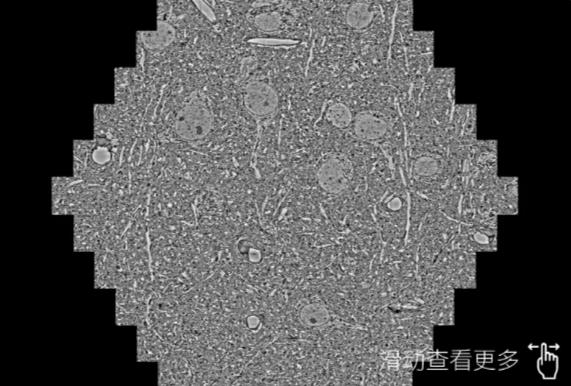

鼠脑切片。左图使用宜昌蔡司宜昌扫描电镜MultiSEM706对165μmx143pm面积区域成像,耗时仅需1.5秒。右图为鼠脑切片中30μm区域放大效果。样品由芝加哥大学B.Kasthuri提供。

使用蔡司高速宜昌扫描电镜MultiSEM对1mm²人脑皮层组织进行高分辨成像,并对其中的各种细胞结构进行三维重构分析。左图展示了2x3mm²组织平面中锥体神经元的三维重构效果。右图显示了局部体积神经元三维重构。图像由哈佛大学chtman实验室提供,渲染图由D. Berger 制作。